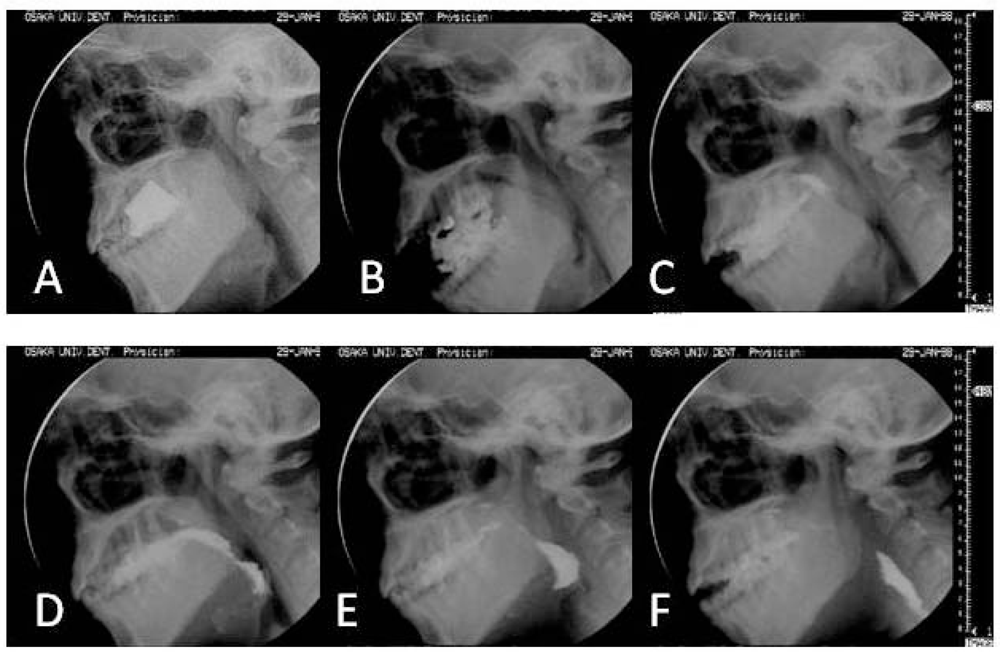

- Ono, T.; Hori, K.; Nokubi, T.; Sumida, A.; Furukawa, S. Evaluation of Mastication and Swallowing of Gummy Jelly by using Digital Subtruction Angiography. Dent. Jpn. (Tokyo) 2005, 40, 57–60. [Google Scholar]